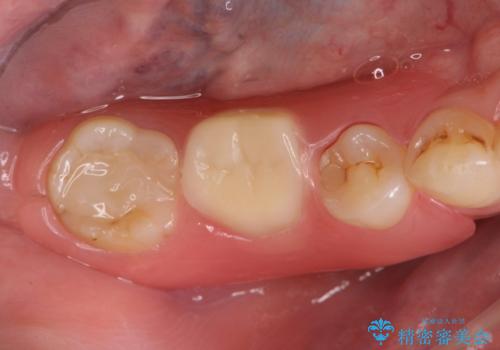

- 欠損し、放置していた奥歯に審美性に優れる入れ歯を作製したいと希望され来院されました。

ノンクラスプデンチャーは、入れ歯に通常ついている目立つ銀色のバネがないため審美性に優れる入れ歯です。

ノンクラスプデンチャーは、ブリッジのように隣りの歯を削る必要もなく、インプラントのように手術も必要ない方法です。